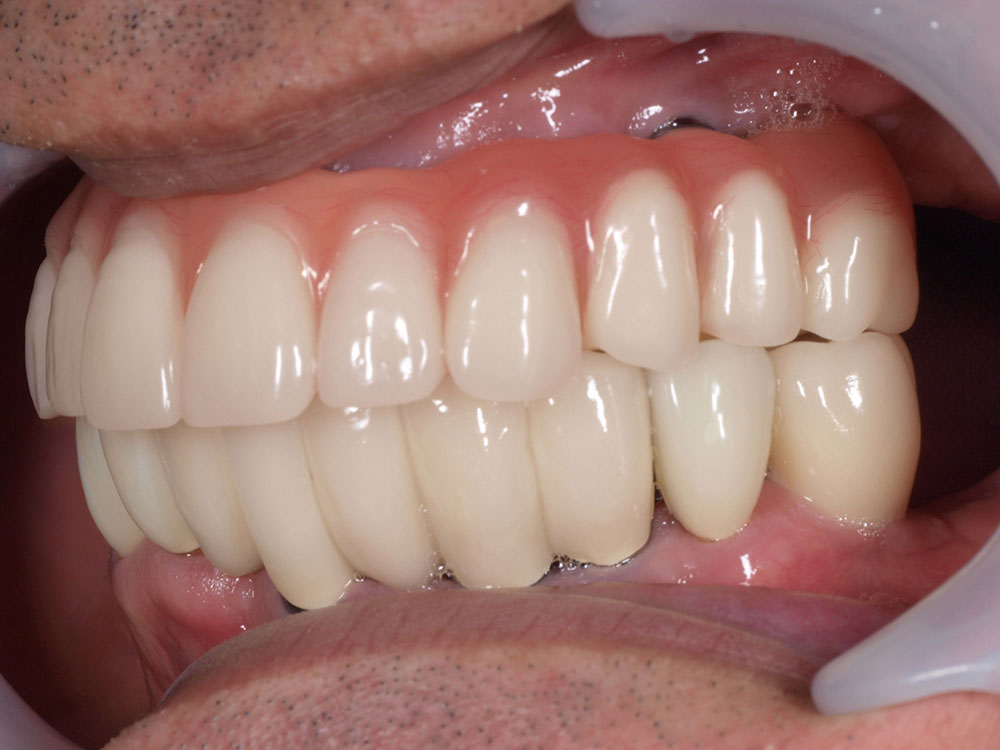

上部構造(人工歯)の装着

インプラントと骨が結合し、口腔内が安定した後、最終的な上部構造を装着します。オールオン4の上部構造は、前歯から奥歯まで連結したブリッジ状の人工歯で、失われた歯茎の部分も人工材料で一体的に作られています。全て一体で作られた人工歯は、歯の大きさ、歯並び、歯茎の引き締まり具合も全て左右対称に理想的な状態にデザインされており、優れた審美性を提供します。唇の張りまで回復するため、清潔で若々しい印象を目指すことができます。

症例紹介

- 主訴

- 入れ歯が合わない。食べにくい。人生を豊かにしたい。

- 処置内容

- 上顎4本で12歯(オールオン4)、下顎4本5歯。

上下抜歯即時埋入、即時荷重(手術当日にインプラントの上に仮歯装着)

- 治療費用

- 上顎:約290万(税込)、下顎:約210万円(税込)

- 治療期間・通院回数

- 上顎:9か月/9回

下顎:6か月/7回

- リスク

- 術後の腫れ、痛み(ピークは3日後、1週間で軽減)

上部構造物、仮歯の破折、人工歯根脱落リスクがあります